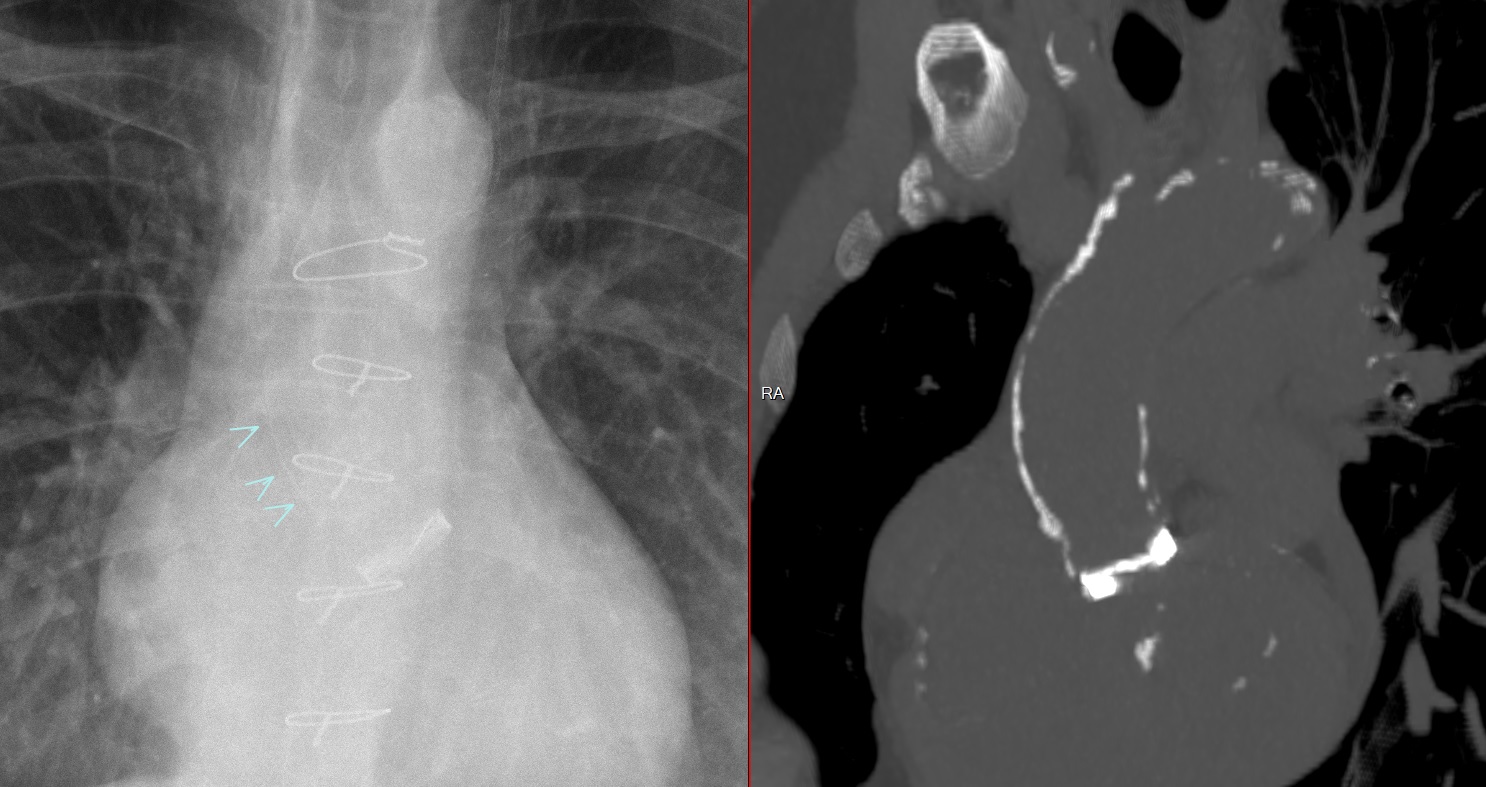

Post-Radique sur Lymphome Hodgkin Irradié

Aorte aorta radique postradique post-radique irradiation radioation irradié calcifiée calcique calcif calcification calcifiee calcifiée